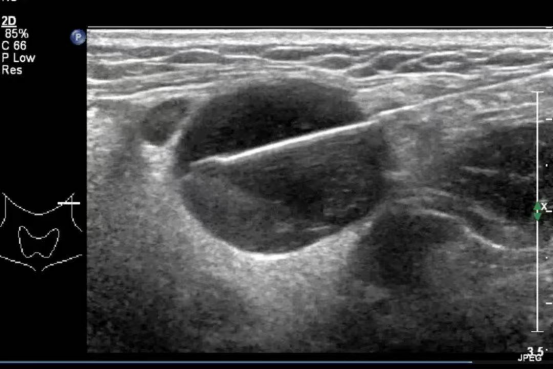

脖子上摸到黄豆大的硬块,按压时有点疼——这种情况你遇到过吗?很多人会觉得上火了”“过几天就好,但如果硬块迟迟不消退,甚至越来越大,可能就是身体在发出求救信号。这时,颈部淋巴结穿刺检查,就能帮你快速找到答案。

简单说,这是用一根细针从肿大的淋巴结里抽取少量组织,送去病理的检查。就像给身体的异常包块做了一次活检,能准确判断是普通炎症、结核感染,还是需要警惕的肿瘤问题。

它的优势很明显:创伤小,全程在局部麻醉下进行,痛感类似打针;速度快,整个操作只要5-10分钟;结果准,病理分析能直接锁定病因,比B超、CT等影像学检查更直击核心